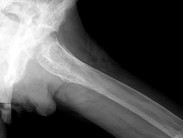

- 单项选择题男,60岁, 左股骨痛1年余,结合图像, 最可能的诊断是 ( )

A、骨纤维异常增殖症

B、Paget病

C、髋关节结核

D、股骨头缺血坏死

E、化脓性骨髓炎